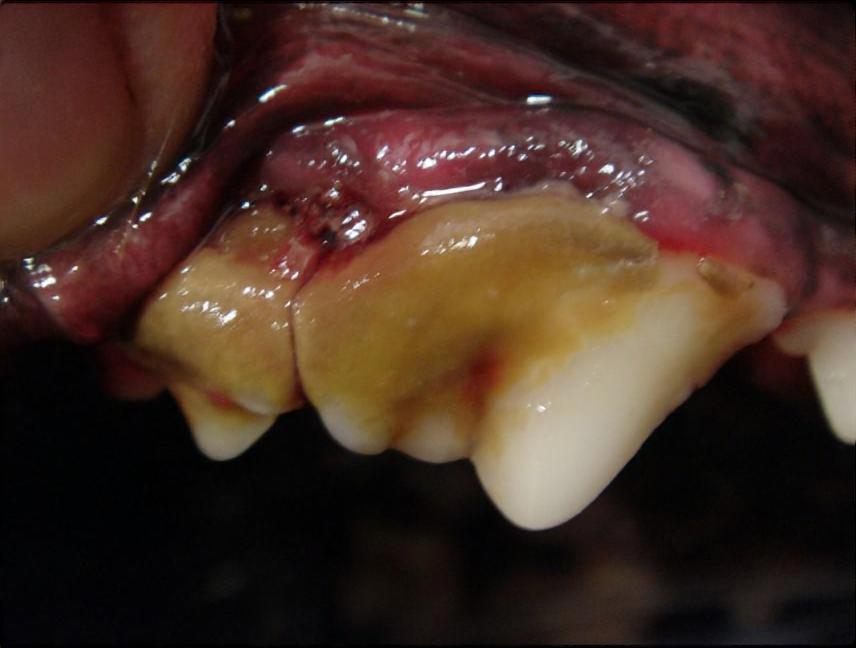

犬や猫の歯は、何もしなければ歯石が付着してきます。

中にはほとんど歯石のつかない子もいますが、たいていは歯石が付き、歯周病を起こします。

歯周病が起こると歯肉の炎症部位から

細菌が体内に入って、さまざまな臓器の疾患を起こします。

年を取ってから起こる病気の多くの原因が歯周病であるといっても過言ではありません。

歯周病を予防するためには、歯石の付着を予防しなければなりません。